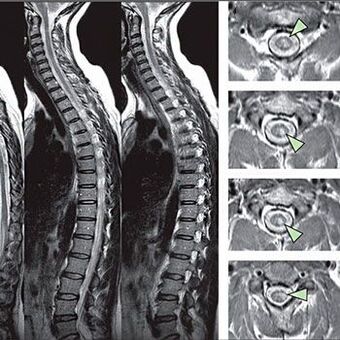

Um die Anzeichen von Sensitivitätsstörungen zu identifizieren, werden spezielle Funktionstests durchgeführt. Die meisten Informationsoptionen für die Diagnose aus instrumentellen Methoden sind die Ausführung eines Röntgenstrahls. Für eine in der Tiefe der Wirbelsäule untersuchte Studie der Wirbelsäule werden jedoch häufig die Magnetresonanztomographie und die CT durchgeführt. Im Falle eines Verdachts auf Krankheiten des kardiovaskulären Systems wird der Patient empfohlen, sich dem EKG -Verfahren zu unterziehen.